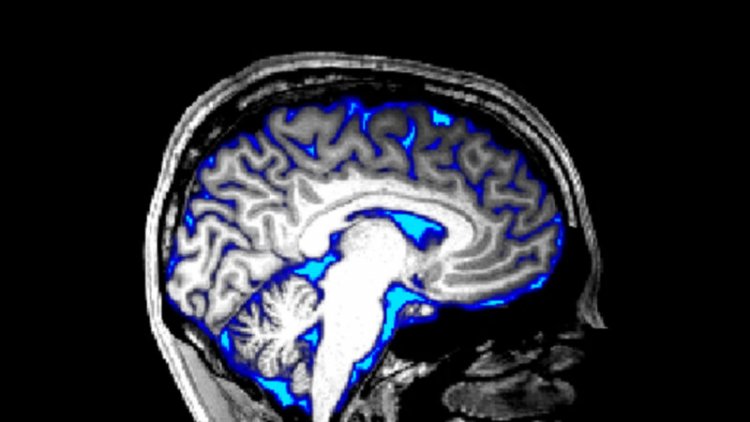

Waves of cerebrospinal fluid which normally wash over brains during sleep can be made to pulse in the brains of people who are wide awake, a new study finds.

The clear fluid may flush out harmful waste, such as the sticky proteins that accumulate in Alzheimer’s disease (SN: 7/15/18). So being able to control the fluid’s flow in the brain could possibly one day have implications for treating certain brain disorders.

In 2019, neuroscientist Laura Lewis of Boston University and colleagues reported that strong waves of cerebrospinal fluid wash through our brains while we slumber, suggesting that one unappreciated role of sleep may be to give the brain a deep clean (SN: 10/31/19). And the team showed that the slow neural oscillations that characterize deep, non-REM sleep occur in lockstep with the waves of spinal fluid through the brain.

Neural activity increased when the flashing pattern was turned on, followed by increased blood flow. Cerebrospinal fluid flow was suppressed while blood flow increased, and then surged into the brain as blood flow ebbed when the stimulation stopped, the team reports March 30 in PLOS Biology.  Longer stimulation produced larger spinal fluid flows, suggesting it was possible to maximize the response.